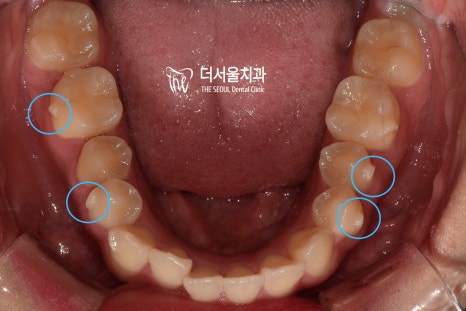

교합면에서 확인해 보았더니

U자에 가까워야 될 악궁의 형태가

사각형에 가까워져 있었습니다.

하악 앞니 뻗침은 생각보다 심하네요.